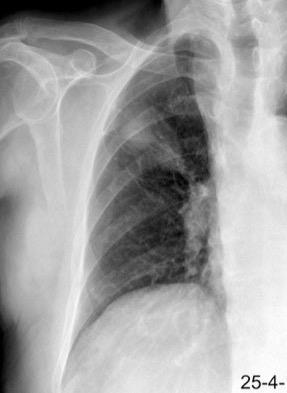

Pliegue axilar Normal

Rehúsa cirugía

2011. Acude por masa axilar

Linfoma NH de cél. B. Invasión Transtorácica.

Afectación axilar